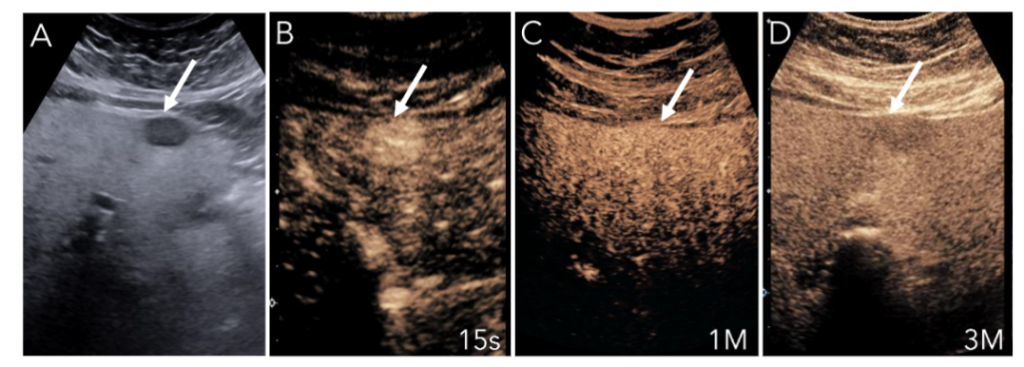

Although LI-RADS was originally validated with CT and MRI, CEUS has similarly been shown to be an accurate imaging method for categorization of liver nodules(24). In a multi-center prospective study, CEUS of 545 nodules with confirmed reference standards demonstrated LI-RADS 5 to have a specificity of 95.1% (95% CI, 94.5%–98.7%)(24). These contrast-based imaging evaluations broadly share similar criteria given the intrinsic enhancement and washout patterns observed in HCC. However, these imaging modalities mutually share challenges in characterizing focal liver lesions like HCC when the liver parenchyma has undergone diffuse fatty changes. Our experience and literature have suggested that although APHE is usually preserved, it is difficult to appreciate washout properties of HCC on MRI with increasing steatosis(25). This absent washout may be secondary to increased background liver hypointensity in fatty liver, which gives the relative appearance of persistent enhancement or isoenhancement when trying to characterize washout in the delayed phase(26). Our experience has shown that CEUS can perform well in identifying nodules and their APHE in fatty liver but can be misleading when assessing for washout in the late phases. We believe this is because of the augmented surrounding enhancement in the late phases caused by the fat, which can portray a picture of “pseudowashout” (Figure 5). Short interval follow-up, repeat injection with a high frequency transducer, and consideration of liver specific contrast enhanced MR are warranted in these situations. Moreover, there is a critical difference that differentiates CEUS from CT/MRI when considering LI-RADS M lesions. In cases of ICC, CEUS and CT/MRI both show APHE, but in the portal venous phase, CEUS shows rapid washout whereas CT/MRI show progressive enhancement (Figure 6)(27). This discordance is thought to be secondary to the purely intra-vascular nature of microbubbles used in CEUS, which is unique compared to the recognized interstitial phase of iodinated and gadolinium-based contrast agents. Although this has yet to be considered in formulating the criteria for LI-RADS M lesions, this finding may further improve the accuracy of CEUS in the diagnosis of focal liver masses.

75-year-old male with MAFLD

A) Greyscale US of a hypoechoic nodule (arrow) in a liver with severe fatty liver disease

B) CEUS shows APHE with centrifugal filling on real-time.

C) CEUS image at 1m shows the nodule remains enhanced, with margins indistinguishable from surrounding liver parenchyma.

D) CEUS image at 3M shows the nodule has the appearance of late weak washout.

This lesion was ultimately found to be focal nodular hyperplasia on pathology, which a benign lesion.

Figure 5: Fatty Liver